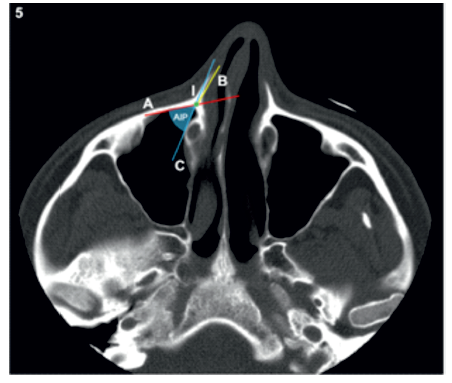

O ângulo da incisura piriforme (AIP) foi medido de acordo com os métodos descritos por Arosio et al.(13). Foi traçada uma linha paralela à face posterior da parede anterior do seio maxilar (linha A) e outra linha paralela à face interna da apófise frontal da maxila (linha B), tendo sido marcado o ponto de interseção entre as duas (ponto I). Foi definida uma terceira linha tangente ao CNL e que passava no ponto I (linha C). A amplitude do AIP foi medida entre as linhas A e C (Figura 5).

A posição do NAAS também foi avaliada. Foi seguido o seu trajeto a partir do canal infraorbitário até à apófise frontal da maxila. Uma vez nesta localização, este foi considerado estar numa posição vulnerável caso se encontrasse posteriormente à linha A e/ou medialmente à linha B (linhas A e B definidas anteriormente) (Figura 6).